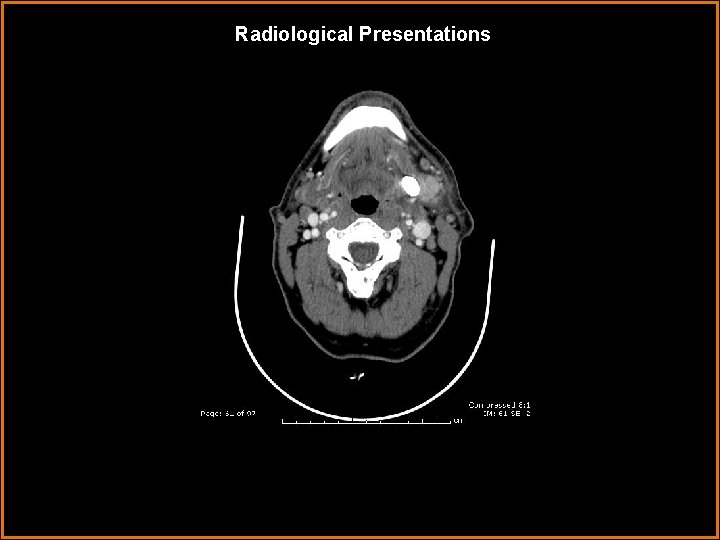

Radiological Presentations

Findings and Differentials Findings: Markedly enlarged, enhancing left submandibular gland with a large 1. 1 cm stone in Wharton’s duct. Differentials: • Submandibular venous vascular malformation – lobulated, heterogenously enhancing mass. • Sialosis – painless bilateral enlargement of salivary glands, usually the parotid glands. Associated with diabetes, obesity, and alcoholism. • Kuttner tumor – pseudomass of salivary gland associated with calcification.

Diagnosis Sialadenitis caused by sialolithiasis.